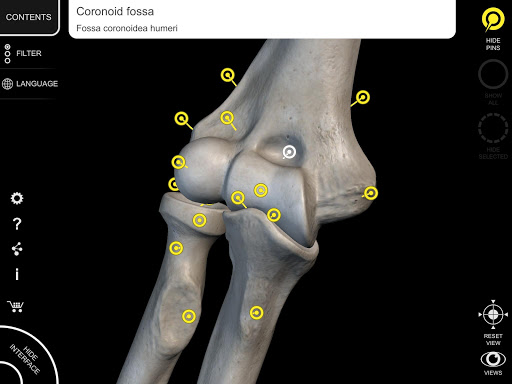

Each bone of the human skeleton has been reconstructed in 3D, you can rotate and zoom in on each model and observe it in detail from any angle.

By selecting models or pins you will be shown the terms related to any specific anatomical part, you can select from 12 languages and show the terms in two languages simultaneously.

• Interactive Pin allow visualization of the term relative to every anatomical detail